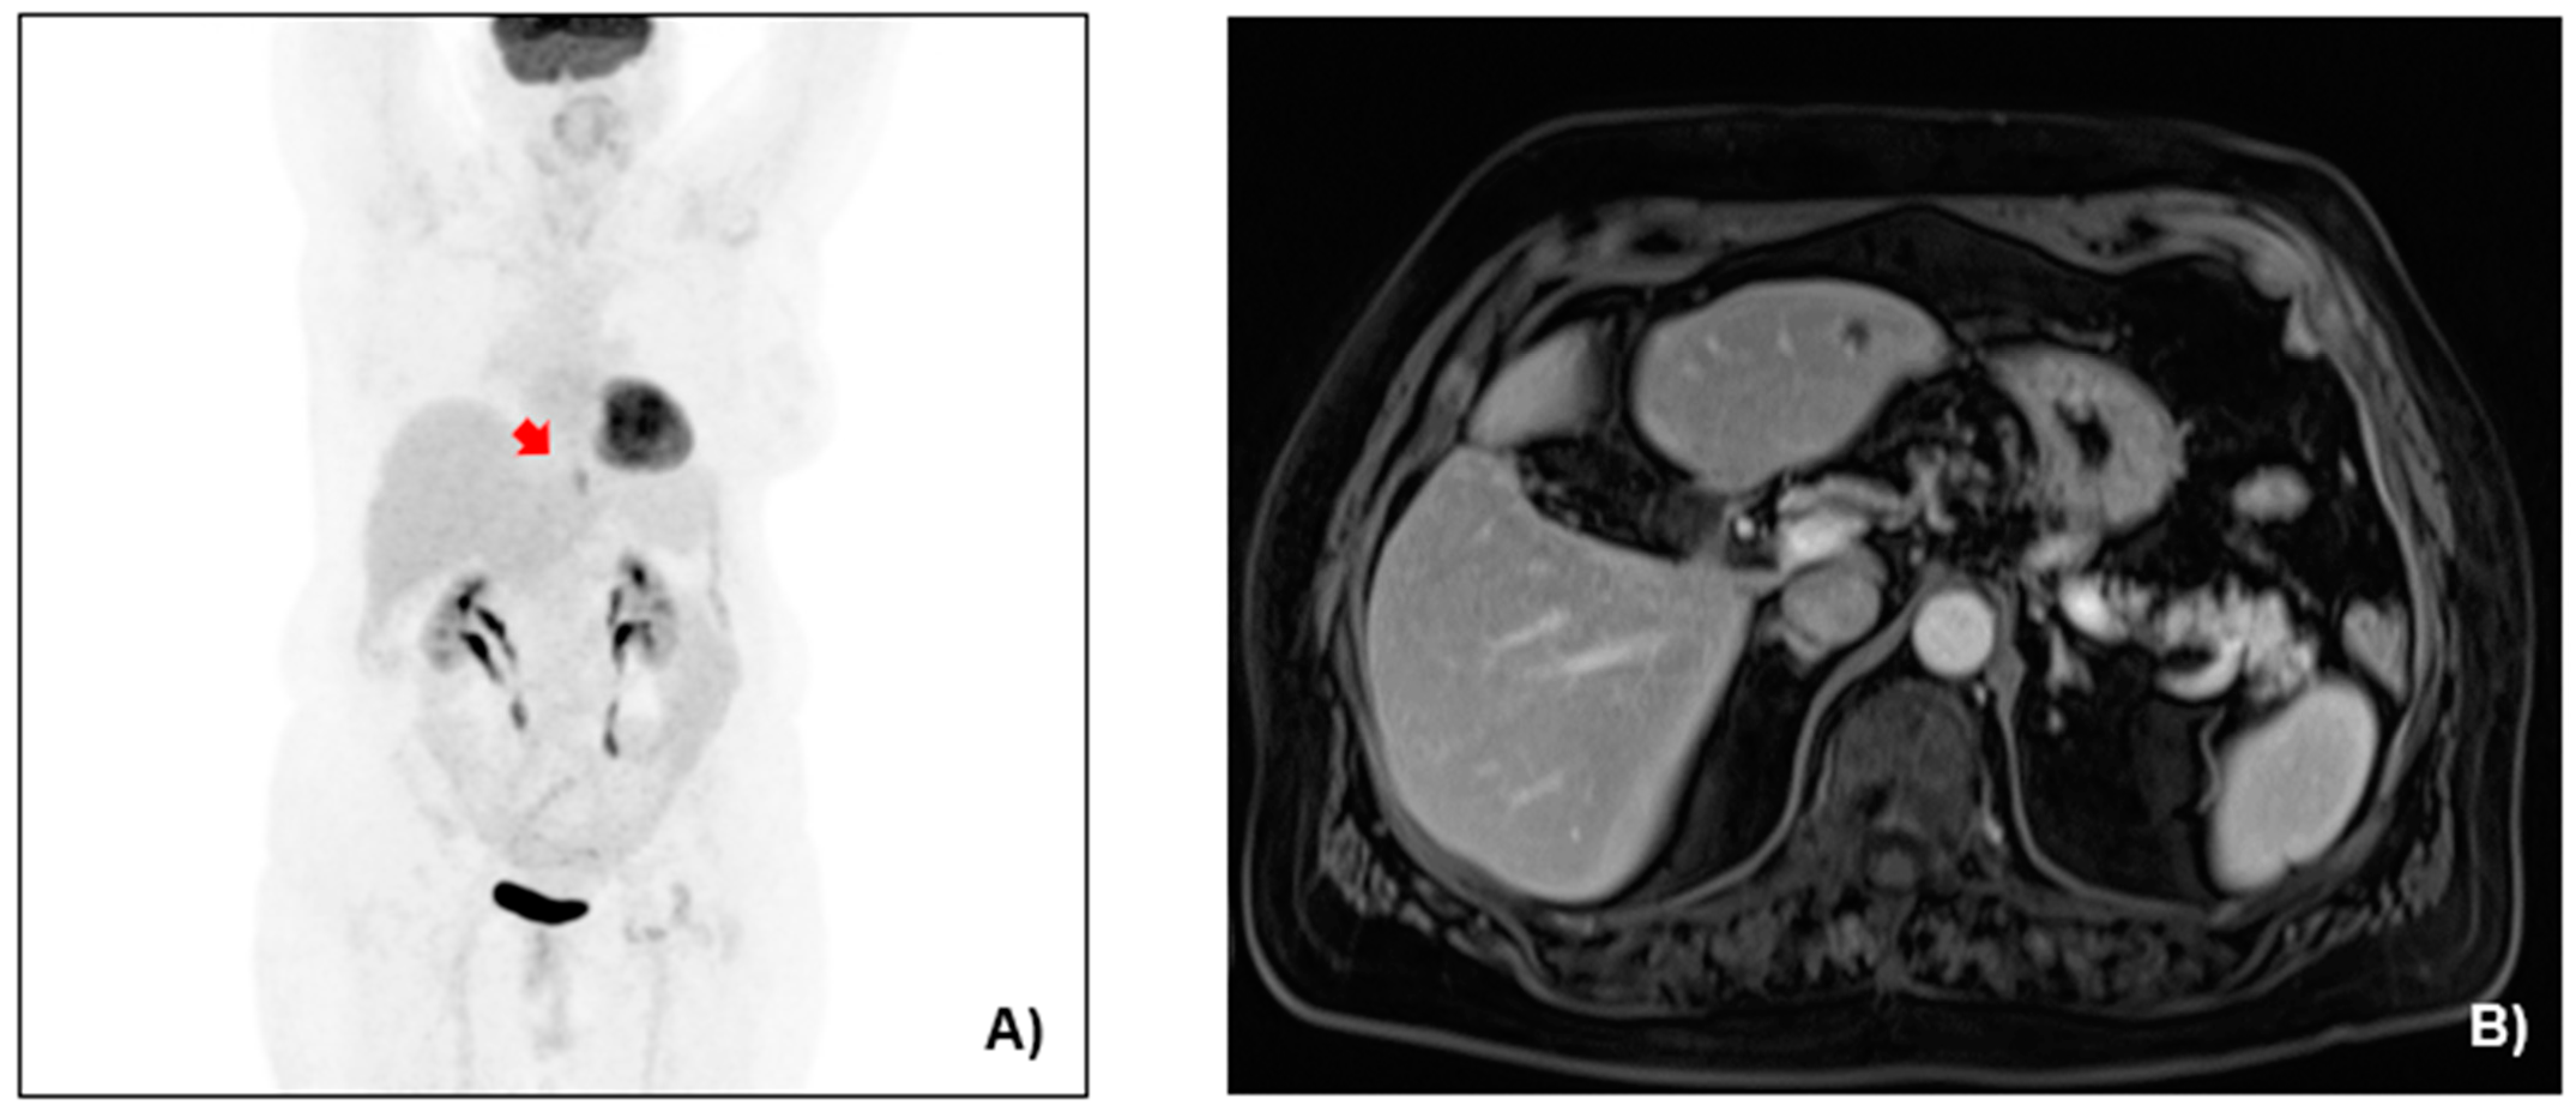

2.2. Case Presentation

3.1. Case Management